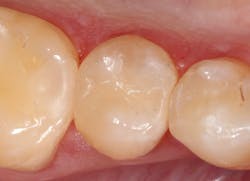

I have found that most posterior teeth can be restored using a single shade. In cases where the tooth structure is very discolored, coupled with a shallow tooth preparation, I opt for an opaque layer beneath my core shade. For anterior cases, the enamel shades offer enough translucency to give the restoration a lifelike appearance. I tend to opt for a core shade to restore chipped incisal edges, and the results have been terrific. Nothing’s worse than a patient coming back with an anterior composite restoration that didn’t hold up; it leads to patients losing confidence in your skills, sometimes negative reviews, wasted chair time, and lost profitability. Polishing this composite is very efficient and effective, and so far, it’s maintained its shine. From my assistants’ perspectives, simplifying my systems made it easier to learn, maintain inventory, and prepare for direct restorations. From my perspective, simplifying composite restorations allows me to reduce chair time, minimize waste, and predictably and efficiently place restorations that my patients love.

Fabricating composite restorations with a simplified system can yield exceptional clinical outcomes and enhance practice profitability.

Results